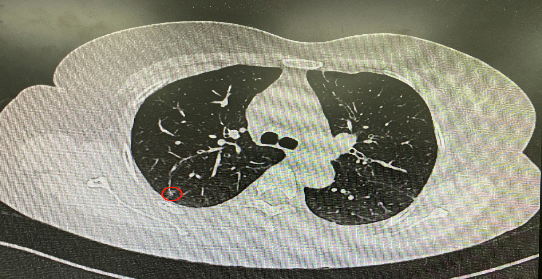

今年54歲的李女士(化名)7月初突然出現(xiàn)右上部腹痛,起初并未在意,以為稍作休息就會(huì)好轉(zhuǎn),但疼痛卻并未消退,持續(xù)了一個(gè)星期。李女士實(shí)在難以忍受,才在家人陪伴下來到西安國際醫(yī)學(xué)中心醫(yī)院就診。胸外科二病區(qū)崔凱主任接診患者后,詳細(xì)詢問病情并查閱檢查資料,經(jīng)胸部HRCT檢查,結(jié)果提示:右肺上葉后段混合密度結(jié)節(jié)影,考慮原位癌可能,即將患者收入胸腔外科二病區(qū)住院治療。

經(jīng)與患者家屬溝通,崔凱主任決定行外科手術(shù)治療。為達(dá)到精準(zhǔn)切除,術(shù)前需進(jìn)行肺小結(jié)節(jié)切除前定位。由于結(jié)節(jié)位于右肺上葉后段,傳統(tǒng)經(jīng)胸外穿刺術(shù)無法抵達(dá)病灶。崔凱主任與呼吸內(nèi)科一病區(qū)歐陽海峰主任討論后,決定擬行LungPro全肺診療導(dǎo)航下染色定位。即術(shù)前通過Lung Pro導(dǎo)航規(guī)劃染色位置,經(jīng)Lung Pro實(shí)時(shí)引導(dǎo)支氣管鏡抵達(dá)既定位置,注入亞甲藍(lán)染色劑標(biāo)記結(jié)節(jié)位置。

使用術(shù)前規(guī)劃系統(tǒng)重建全肺3D模型,并于外科醫(yī)生討論染色位置,最終確定標(biāo)記染色點(diǎn)—右肺上葉后段b亞段(RB2b)。術(shù)中使用P290(4.9mm外徑)標(biāo)準(zhǔn)支氣管鏡,根據(jù)導(dǎo)航術(shù)前規(guī)劃路徑,Lung Pro實(shí)時(shí)導(dǎo)航下,GS鞘管進(jìn)入RB2b遠(yuǎn)端官腔外病灶并注射亞甲藍(lán)染色劑。

一切準(zhǔn)備就緒,7月15日,崔凱主任團(tuán)隊(duì)聯(lián)合歐陽海峰主任團(tuán)隊(duì)為患者行單孔胸腔鏡下右肺上葉后段切除術(shù),手術(shù)用時(shí)128分鐘順利完成。進(jìn)入胸腔后,亞甲藍(lán)染色部位明顯,患者發(fā)生癌變的右肺上葉后段被成功切除。術(shù)后標(biāo)本根據(jù)染色部位迅速找到結(jié)節(jié),剖開位置兼染色位置和病灶完全符合,行術(shù)中冰凍后快速送病理檢查。經(jīng)術(shù)后病理檢查,明確診斷為(右肺上葉)原位腺癌。